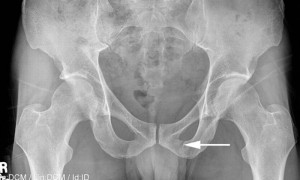

Наиболее достоверный способ определения переломов лонной кости таза и других травм является рентгенография. Однако важно выполнить не только обзорный снимок таза, но и прицельную рентгенографию. Боковые снимки помогают визуализировать смещение отломков кости.

Важным приемом при постановке диагноза является пальпация, которую выполняет только врач. Он делает это аккуратно и тщательно. Так можно установить точное место локализации, крепитацию и так далее.